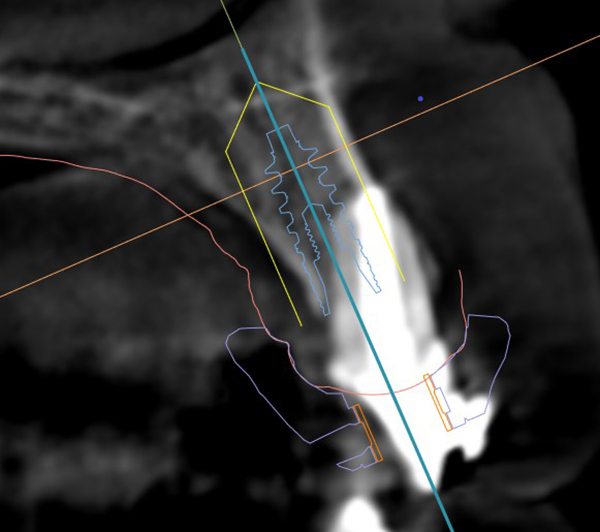

Extraction after forced eruption can allow for a much more favorable implant site compared with extraction alone. This is possible because the tension applied to the periodontal ligament during orthodontic tooth movement stimulates osteoblastic activity to induce new bone formation. As the tooth moves coronally during extrusion, soft tissue and bone attached to the periodontal fibers migrate in the same direction. As a result, forced eruption can be used to enhance the quality and quantity of both hard and soft tissue of future implant sites.

The special report presented below illustrates how orthodontic extrusion was successfully used to improve the periodontal architecture prior to the placement of two adjacent implants in the esthetic zone and thus allowed for a more ideal restorative result.